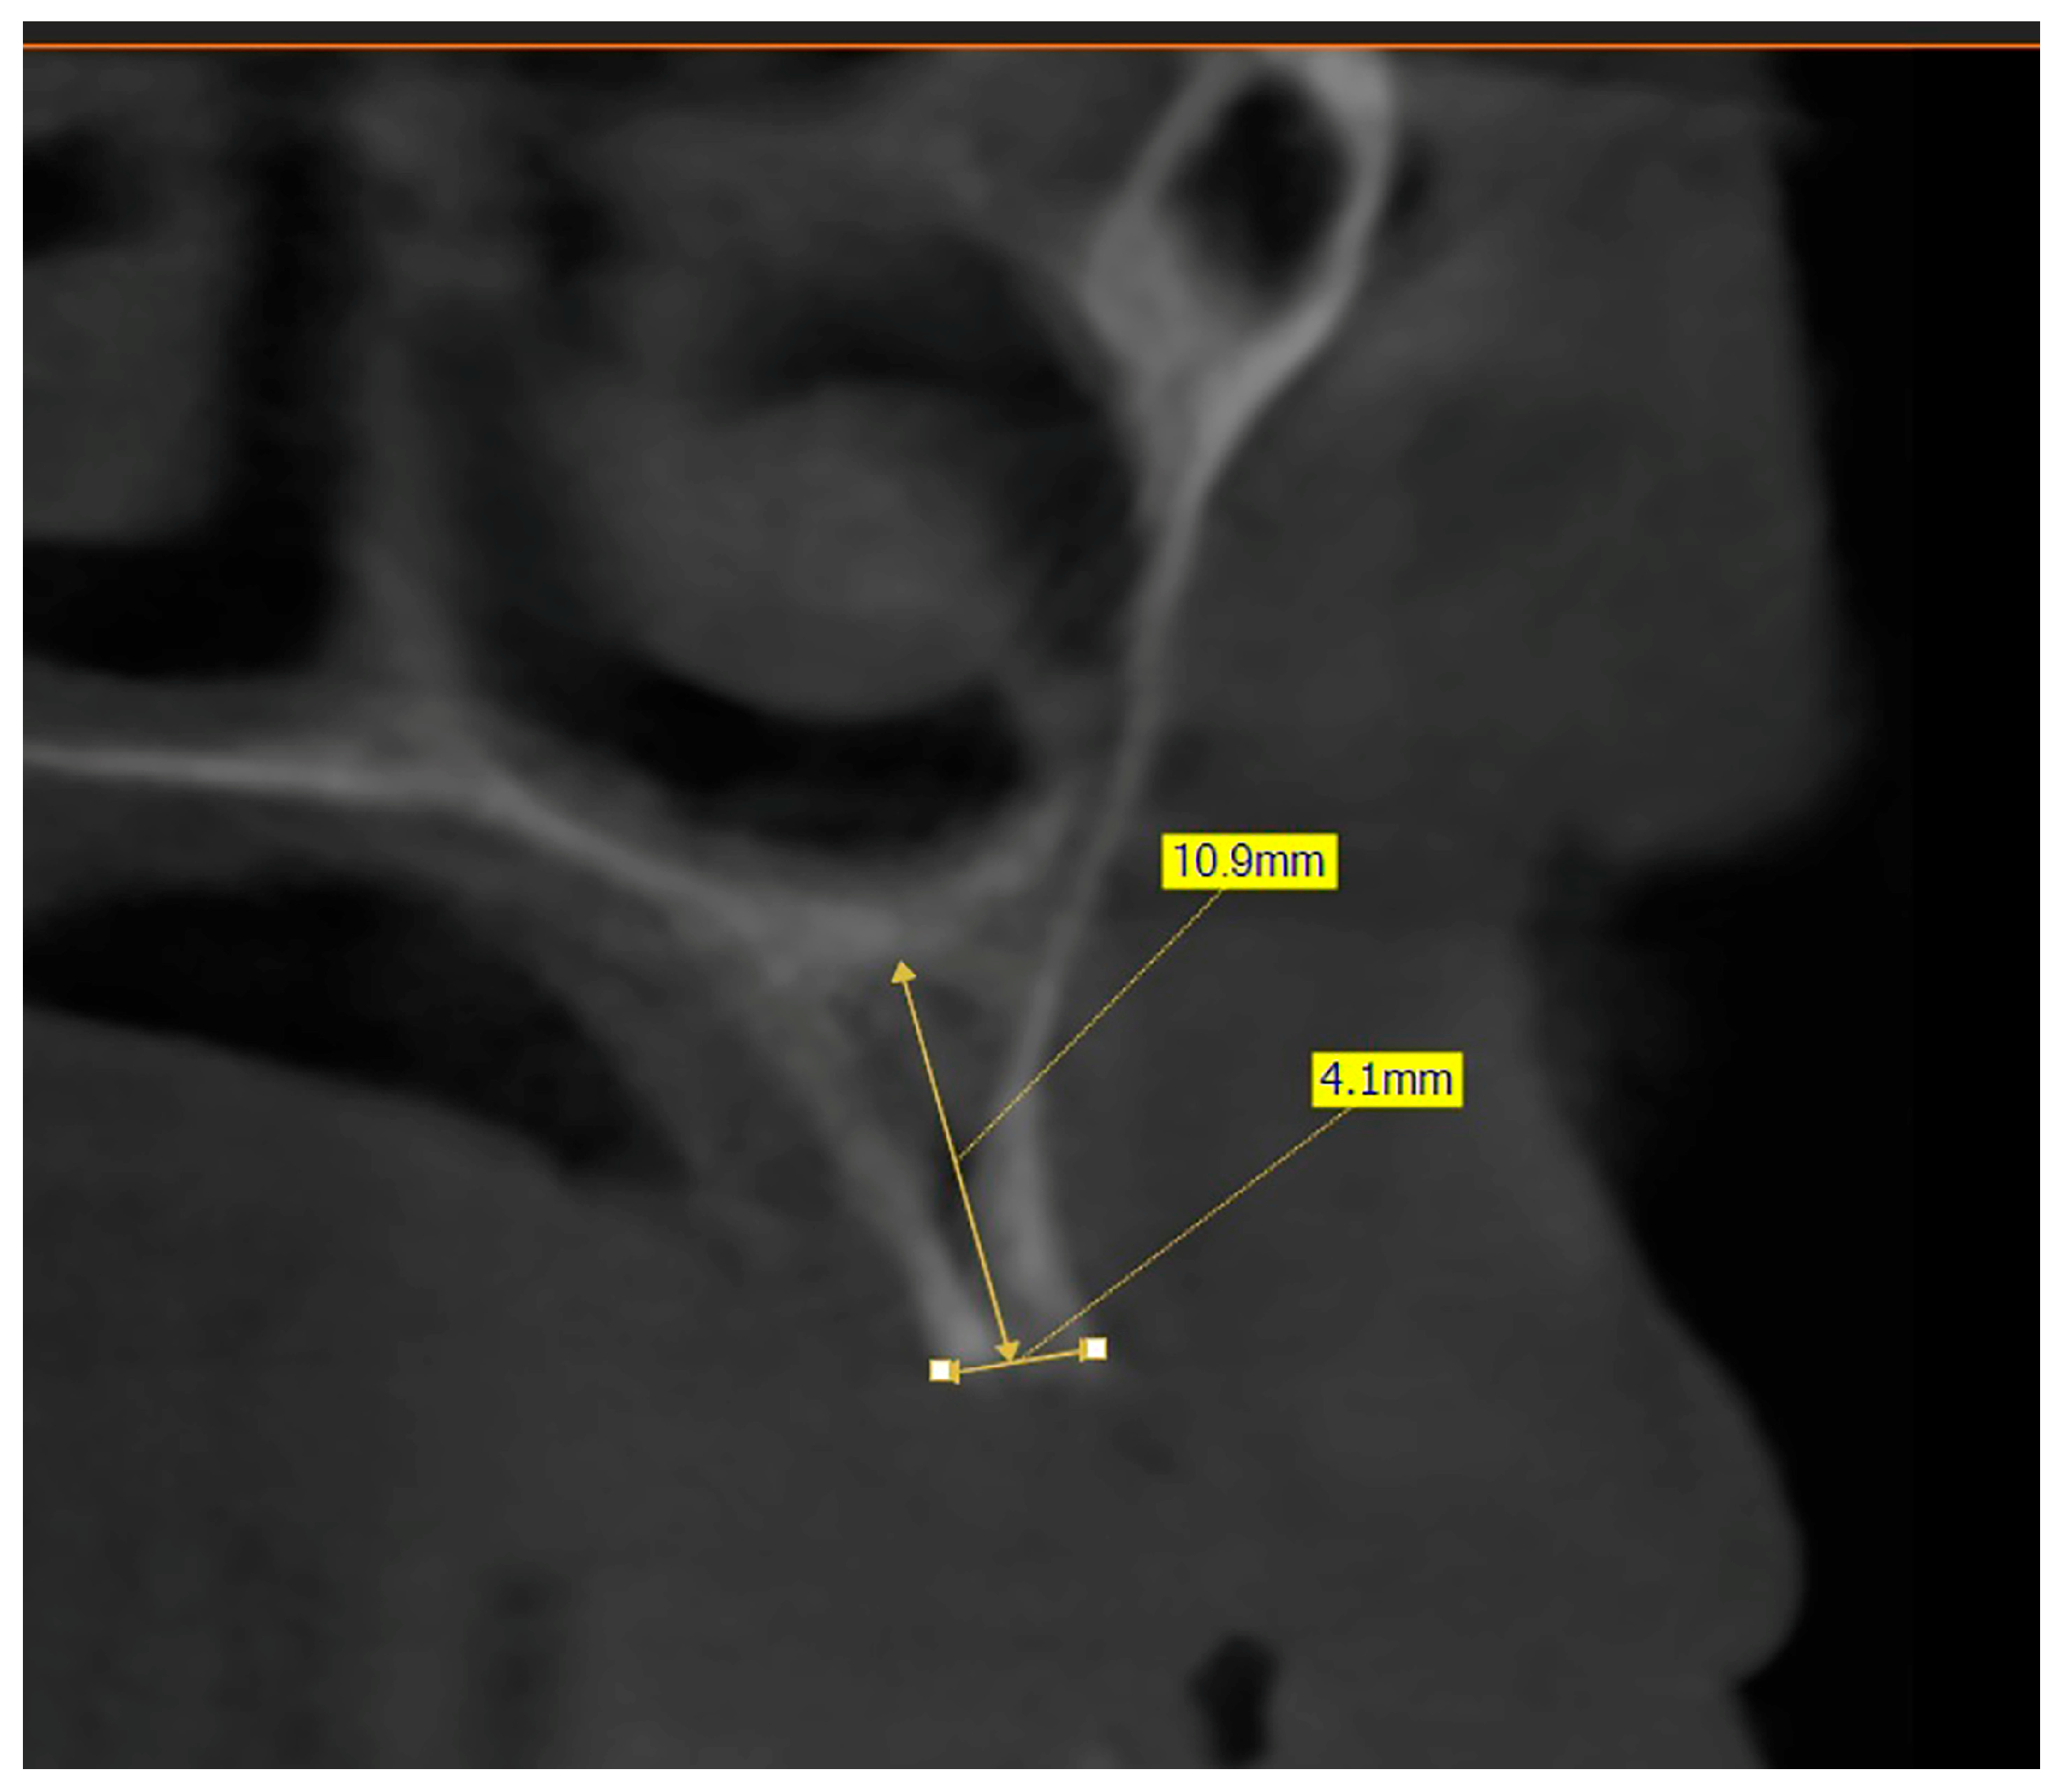

The preoperative plan included a detailed history, clinical examination, and analysis of 3D CBCT images. Detailed measurements of bone height and width at the sites of the future implants (at the level of planned position of implant platform), as well as bone density, were performed on cross-sectional CBCT images (Figure 1 and Figure 2) by an investigator who was not involved in the surgical procedure. Prior to the surgery, an oral rinse of chlorhexidine digluconate solution 0.2% (Hibideks DAP®, Galenika, Beograd, Serbia) was administrated to all the patients for 1 min.

Figure 1. Bone measurement on a cross-sectional image—CBCT (Green X™ 12®, Vatech, Prague, Czechia).